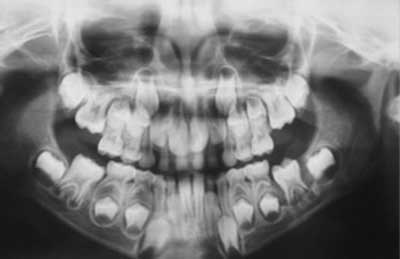

Foto 1: Rx pre 10-2003

Foto 1: Rx pre 09-1999